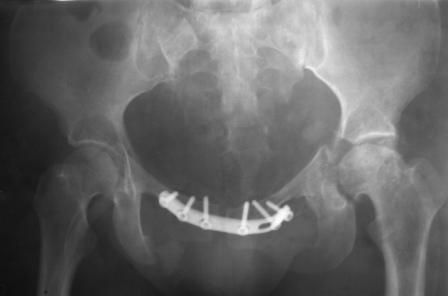

Уважаемые коллеги! Пациентка 32 года с застарелым повреждением таза, после остеосинеза лонного сочленения пластиной. Посоветуйте с выбором тактики и методик лечения.

Получила травму в феврале 2004г в г.Лобытнанги ЯНАО Тюм.обл. Через неделю после поступления выполнен остеосинтез лонного сочленения пластиной. 1,5 месяца на скелетном вытяжении. В последующем ходит при помощи костылей с нагрузкой на правую ногу. Имеется нестабильность половин таза, неправильно-консолидированный перелом левой вертлужной впадины, невропатия седалищного нерва слева. В результате невропатии седалищного нерва сформировалась эквинусная установка левой стопы,парестезии по подошвенной поверхности.

Направлена к нам для устранения патологической установки стопы и эндопротезирования левого тазобедренного сустава, также имеется миграция шурупов пластины, фиксирующей лонное сочленение.

Клинически: ходит на костылях с нагрузкой на правую ногу. Левая стопа в эквинусе. Осевая нагрузка на левую н\конечность болезненна в области левого тазобедренного сустава, при прикосновениях к подошвенной поверхности стопы у пациентки чувство зжения. В левом коленном суставе полный обьем движений, в левом тазобедренном резко ограничено отведение и ротация, укорочение левой н\конечности на 2,5 см. При полипроекционной и функциональной Р-графии выявлена нестабильность левого КПС и лонного сочленения, консолидированный в порочном положении поперечный оскольчатый перелом левой вертлужной впадины с центральным смещением головки бедра. Нами выполнена коррекция деформации левой стопы. Планируется выполнить введение 2 канюлированных илиосакральных винтов слева, реостеосинтез лонного сочленения реконструктивной пластиной, после заживления ран - тотальное эндопротезирование левого тазобедренного сустава.